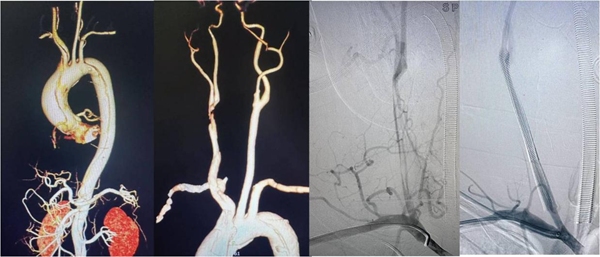

凭借极致的精准操作,团队通过手术切开暴露桡动脉,成功建立介入治疗通路,顺利在堵死的右侧颈动脉里植入2枚支架,把被夹层压扁的血管完全撑开。术后造影显示,患者右侧大脑的血流瞬间恢复通畅,第一关圆满成功。

神经介入手术收尾的瞬间,宋国宝教授团队立刻无缝接力,开启第二关的心脏拆弹。团队在低温麻醉、人工心肺机的支持下,精准完成了撕裂血管的全程修复:换掉从心脏出口到主动脉弓的全部撕裂血管,补好了被撕坏的冠状动脉开口,同时修复了受损的心脏瓣膜,彻底拆除了心脏上的致命“炸弹”。